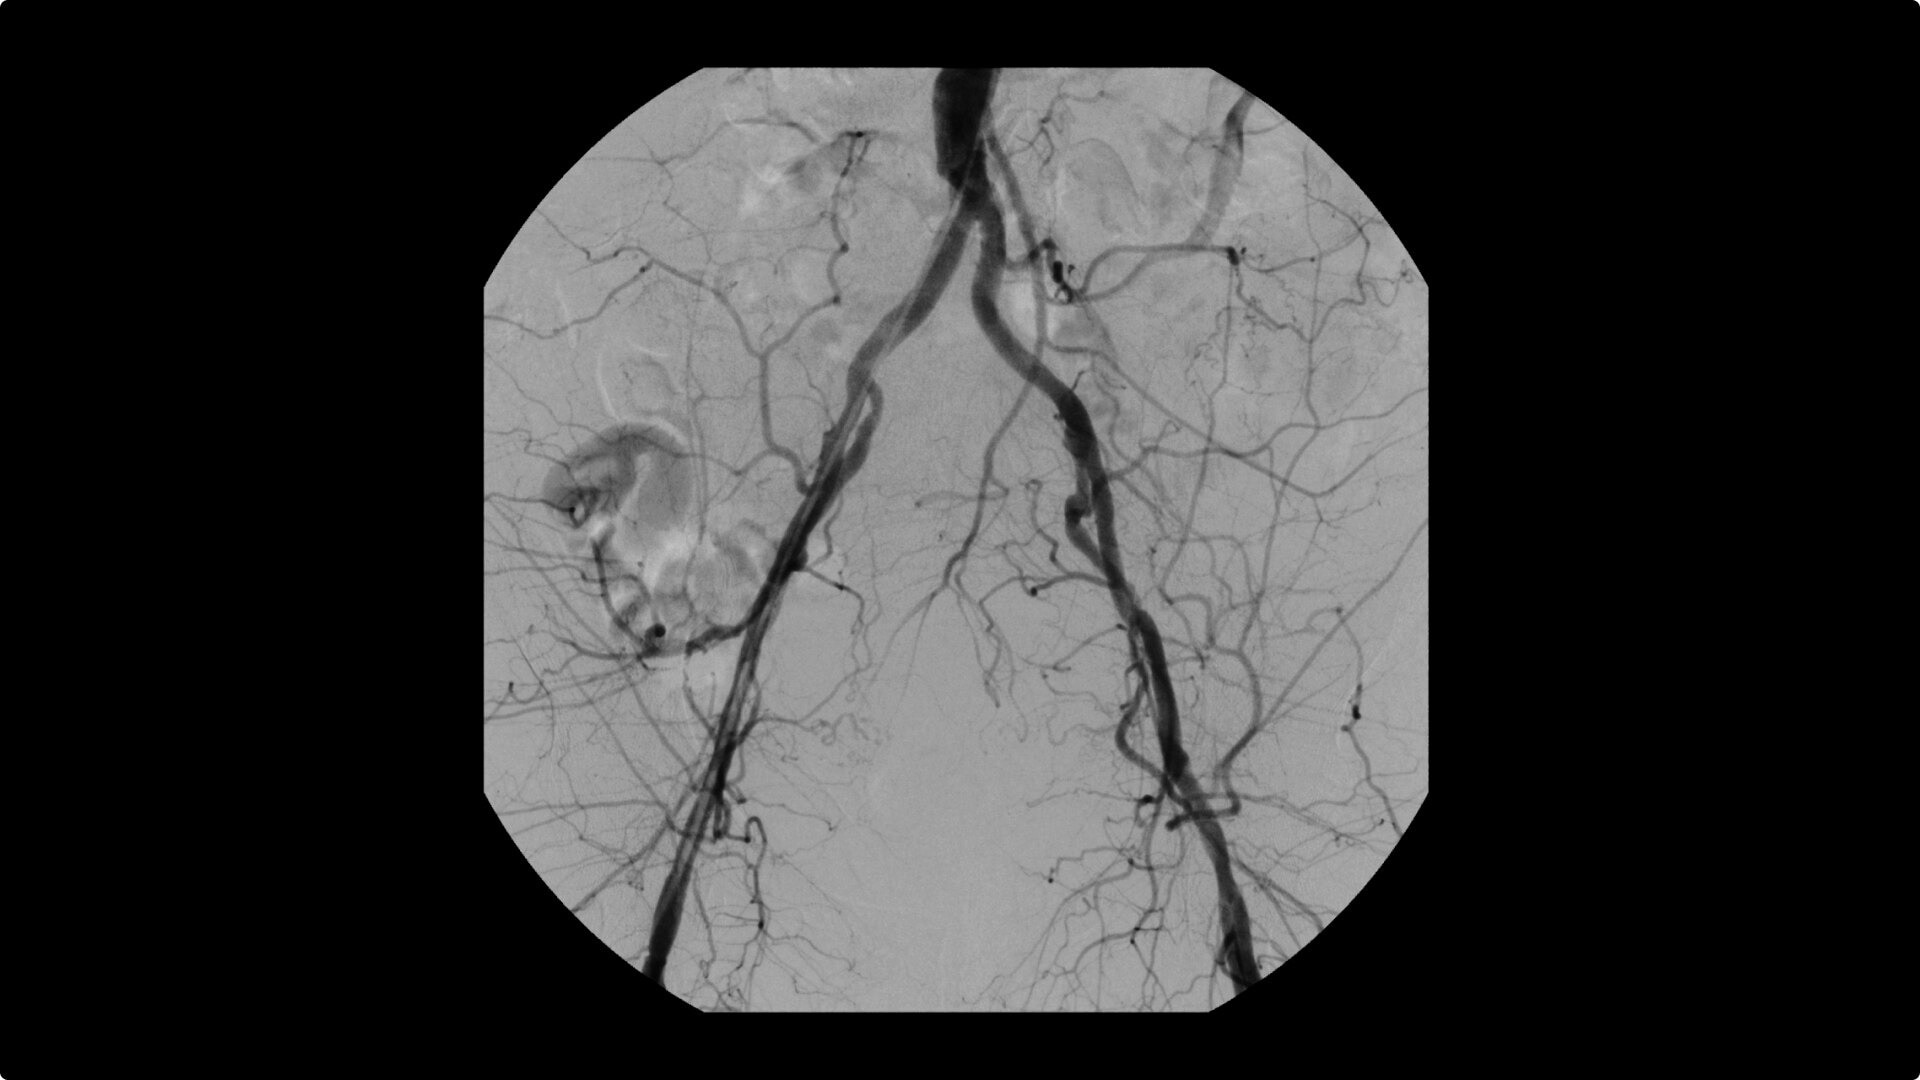

OEC C-arms are used by interventionalists and surgeons to obtain vascular imaging during peripheral to contrast run-off procedures. Superb resolution, even in the presence of motion, enables easy identification of anatomical landmarks and the extremity of the catheter, even as catheter tip moves.

Clearly see 0.014” guidewires in chest and abdomen region or 0.008” guidewires in peripheral vascular with the OEC Elite CFD with a flat detector, image processing advancements and 4K viewing display.

Perform a full leg Bolus Chase in one contrast run with a Preset Profile that includes Motion Tolerant Subtraction, that dynamically adjusts image quality based on presence of motion.

During contrast run-off procedures, easily select contrast type with positive (e.g. Iodine) or negative (e.g. Carbon Dioxide) during subtraction. The OEC Elite CFD cardiovascular package also includes Roadmapping.

Complex vascular procedures require powerful imaging systems. OEC premium C-arms perform in a variety of procedures such as:

• Recanalization and stent placement in iliac arteries

• Recanalization of the superior mesenteric artery

• Stent implant in peripheral artery